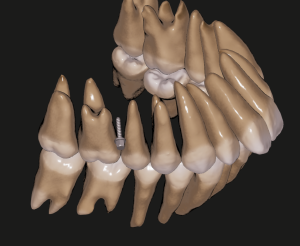

一人ひとりの歯列、顎骨の状態に合う理想的な咬合を作るためのシミュレーション、現実的な歯の移動限界の把握に利用したりしています。

(矯正用インプラントの位置決め。この部位に使うわけではないですが、イメージとして。)

※スタッフの歯列、CTデータです。許可を得て、使わせていただきました。